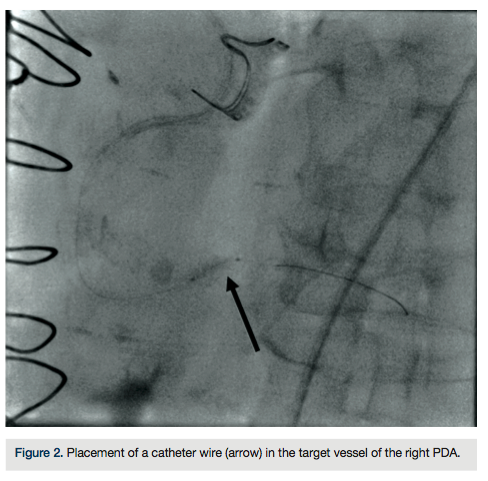

A 75-year-old female with a past medical history of coronary artery disease with previous coronary artery bypass grafting with left internal mammary artery (LIMA) to left anterior descending (LAD) artery, saphenous venous graft (SVG) to ostial medial (OM) branch, SVG to postero-lateral (PL) branch, and bioprosthetic aortic valve replacement presented with progressive dyspnea on exertion associated with substernal chest pressure. She presented with no ECG changes or elevation in cardiac biomarkers. Despite optimal medical management, she continued to endorse chest pain and thus underwent cardiac catheterization for evaluation of her coronary anatomy. Catheterization revealed a patent LIMA to LAD and SVG to OM, moderate disease in the SVG to PL graft, and a new, severe subtotal occlusion of the posterior descending artery (PDA) from the right coronary artery. We proceeded with intervention to this vessel using a 6 French (Fr) 0.75 Amplatz guide catheter. The index lesion was crossed with a Balance Middle Weight (BMW) guide wire (Abbott Vascular), with difficulty. Predilation was attempted with a 2.5 x 12 mm Apex balloon (Boston Scientific), but could not be advanced beyond the mid PDA. A GuideLiner catheter (Vascular Solutions) and a 1.25 x 10mm Sprinter Legend balloon (Medtronic) were advanced to the distal right coronary artery where they became resistant to advancement. The balloon was briefly inflated, but would still not advance. It was noted to have ruptured and despite aggressive tugging and pushing, could not be removed. The GuideLiner catheter could not be advanced further into the vessel to help free the balloon. It could also not be removed entirely, as it contained the shaft of the balloon. Eventually, with applied tension, the balloon shaft avulsed and remained in the distal RCA. Two different snares and two QuickCross catheters (Spectranetics) were advanced over the guide wire, but could not reach the site of the balloon. Given the tortuous anatomy and degree of calcification, it was determined that no other device or stent could be delivered, and thus the delivery wire was removed. Final angiography revealed TIMI-3 antegrade flow into the PDA, but with an obvious retained balloon tip and associated filling defect. Severe residual stenosis of the index lesion also remained. The patient remained hemodynamically stable throughout the procedure and asymptomatic subsequently. No ECG changes were identified and no regional wall motion abnormalities were seen on